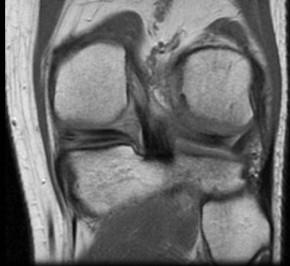

问题 男,32岁,左膝关节有外伤史,膝关节部有疼痛,上下楼梯时加重,请结合所提供的图像,选择最佳选项 ( )

选项 A、胫骨骨折 B、后十字韧带撕裂 C、前十字韧带撕裂 D、内侧半月板外周后角垂直撕裂 E、未见异常

答案 D